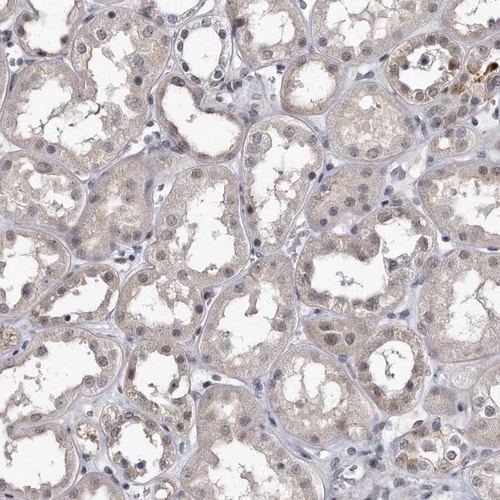

Immunohistochemical staining of human testis shows moderate cytoplasmic positivity in cells in seminiferous ducts and leydig cells.